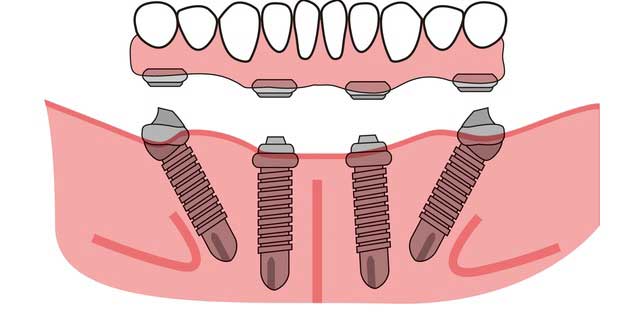

Grand Parkway Smiles is a multi-specialty dental implant, oral surgery, and general dentistry center in Katy, TX. Near Cinco Ranch. Our dental specialists have a combined 120+ years of experience including Dr. Ryan Smart oral surgeon, Dr. David Gomez dental implantologist, Dr. Louis Bosse prosthodontist, endodontist, and pediatric dentist—provides comprehensive, pain-controlled care under one roof. Services include dental implants, All-on-4 and snap-in dentures, wisdom teeth removal, root canals, extractions, full-mouth restoration, TMJ/TMD care, cosmetic dentistry, and IV sedation for anxiety or complex procedures. Same-day emergency visits available. We accept most PPO dental insurance and offer in-house payment plans and financing.